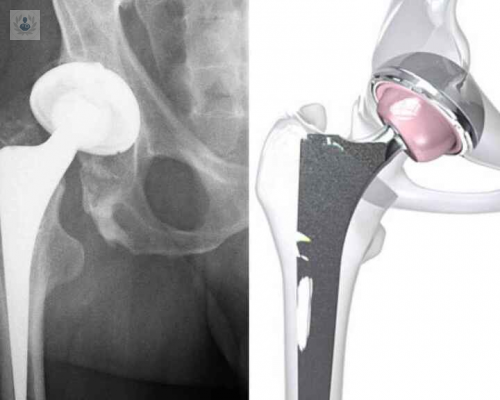

La artrosis de cadera es un padecimiento crónico y para el tratamiento de casos muy avanzados se puede indicar el reemplazo de cadera. Se trata de un procedimiento quirúrgico extremadamente reglado y estandarizado, el cual debe ser realizado por un equipo de especialistas para garantizar los mejores resultados. Conozca los detalles sobre esta intervención